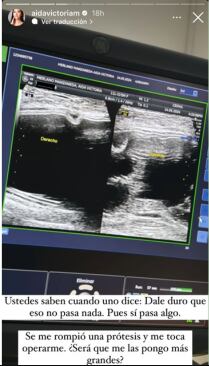

Por medio de sus más recientes historias de Instagram, perfil en el que suma más de 6 millones de seguidores, Aida Victoria Merlano preocupó a sus fans al confesar que tuvo que ser intervenida por un profesional luego de presentar algunas anomalías con una de las prótesis mamarias que se implantó hacer varios años.

Según confesó la mujer en el video, una de las prótesis no se encontraba en la posición adecuada. Por el contrario, estaría ‘fuera de lugar’, lo que le estaría causando cierta incomodidad física y dolor.

Días atrás, la mujer de 24 años de edad había revelado por medio de su perfil que una de sus prótesis se había reventado y no contaba con las condiciones adecuadas para permanecer dentro de su cuerpo, razón por la cual, decidió buscar ayuda profesional para buscar una solución y garantizar su salud.

“¿Ustedes saben cuando uno dice, dale duro que no pasa nada? Pues sí pasa algo. Se me rompió una prótesis y me toca operarme, ¿será que me las pongo más grandes?”, escribió.